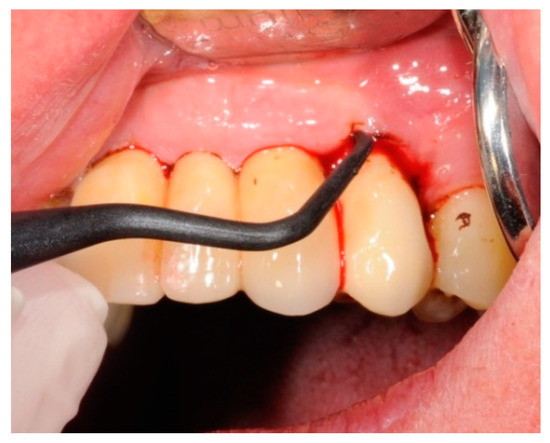

4.5. Test Substances and Administration